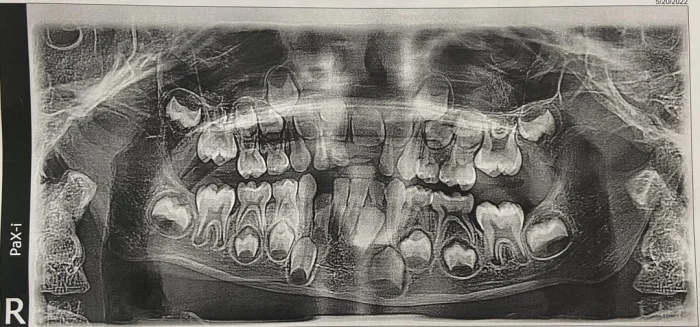

1. «В прошлом месяце я пришёл на чистку зубов к стоматологу. Я упомянул, что чувствую онемение в одном из зубов. Я был в ужасе, когда увидел опухоль, которая разрушает челюстную кость»

2. Это объясняет боль